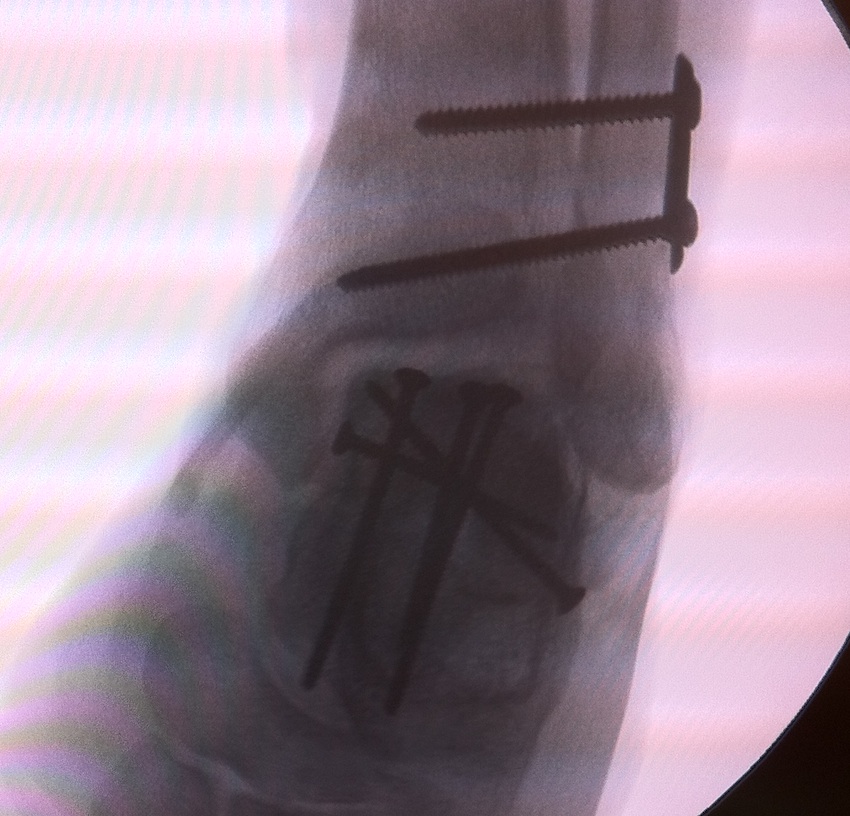

Cannulated screws

Xrays

| AP | Lateral | Canale View |

|---|---|---|

| Entry point of the screws |

Evaluate neck reduction

|

Evaluates the neck reduction |

Lateral off articular surface Medial through articular cartilage |

Depth of screws |

Beam angled 75o to foot Foot 15o pronated |

1. Retrograde (anterior to posterior) into posterior talus body

A. Lateral screw

- insert proximal to articular surface of head on lateral side

- bone is very curved here

- can lag screw as usually no comminution

B. Medial side

- insert through articular surface

- countersunk screws through articular surface

- avoid lag screw techniques medially as may compress comminution into varus

AP, Canale and Lateral xray

Retrograde screws